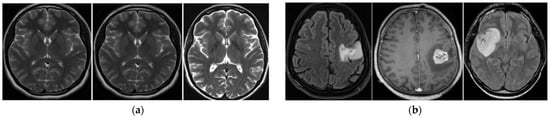

In Figure 11, we show some example error cases caused by individual method, including the SVM-, MLP-, and FS-based methods. As shown in this figure, all these methods (SVM-, MLP-, and FS-based methods) can falsely classify a non-tumor image as a tumor image when the input images contain noise and/or high-contrast brain regions, as shown in the images on the left side of this figure. When the size of the tumor is relatively small or unclear, these methods can falsely classify a tumor image as a non-tumor image, as shown in the images on the right side of this figure.